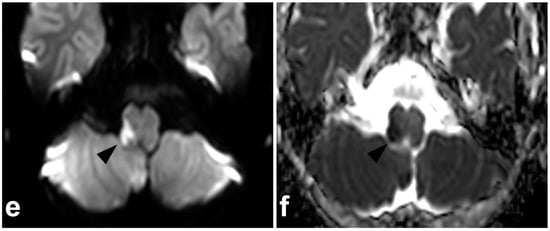

6. Spinal Cord Injuries

The use of MRI in acute spinal cord trauma was first described in 1983 [60,61] and it has been the gold standard in imaging these injuries ever since. T1-weighted, T2-weighted, and STIR sequences are the cornerstones in assessing the cord [49]. Diffusion-weighted imaging (DWI) and diffusion tensor imaging (DTI) might be useful in detecting subtle injuries and as a prognostic biomarker, but their role in clinical practice is not fully established yet [62,63,64,65,66]. Susceptibility-weighted imaging (SWI) or T2*-weighted sequences might increase the sensitivity in the case of small intramedullary hemorrhages but are technically challenging to obtain due to pulsation and motion artifacts [67,68]. Cases of spinal cord injuries are presented in Figure 15 and Figure 16.

Figure 16.

(a) Sagittal T2-weighted. (b) Coronal STIR. (c) Axial T2-weighted (dotted line in the image (a)). A 2-year-old female, severe cervical fracture–dislocation after a car accident. The spinal cord is transected. The cord caudally to the transection site (arrows) is dislocated posteriorly and on the right side of the cranial end of the transected cord (arrowhead). An extensive hematoma is seen around the fracture.